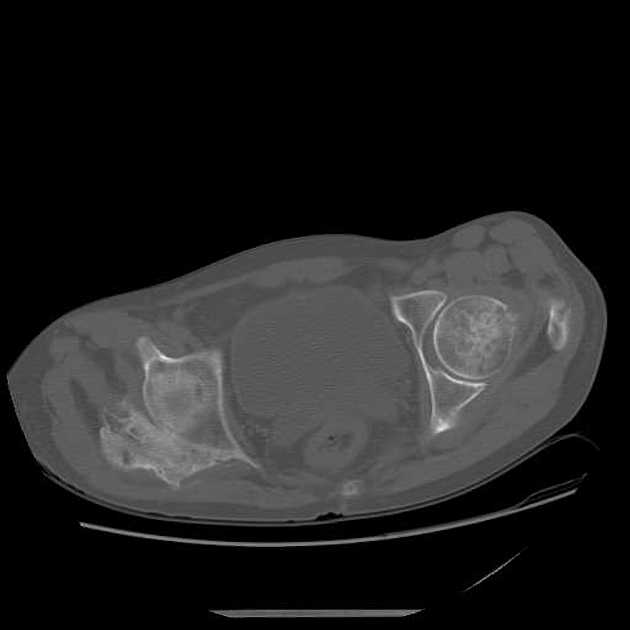

Figure 1 demonstrates early calcification of a myositis ossificans lesion in the left triceps muscle. As is characteristic, there is an outer shell of bone with a lucent central region. Figure 2 is a more mature, well-defined lesion with a dense periphery at the medial aspect adjacent to the femur.

CT may be useful in the visualization of a lesion. Figure 3 demonstrates a lesion posterior to the right acetabulum. It demonstrates a partially corticated periphery and partial cleft separating the lesion from the acetabulum. Figure 4 is an interesting example of an MO lesion in the paraspinal musculature, with ossified periphery and lucent center.

Radiographically, findings may appear as early as 3 to 4 weeks post-injury. Initially, there may be a hazy increase in density in the soft tissues. With time, the bone formation will be noted at the periphery of the lesion, forming a shell. Progressive ossification of the lesion may follow, characteristically with a denser periphery and a relatively lucent central region. The lesion is usually mature at 2-6 months. Typically, a radiolucent cleft is seen separating the lesion from the underlying bone. After reaching maturity, the lesion usually will regress in size. This appearance is a key to differentiating myositis ossificans from parosteal osteosarcoma, which is the main differential diagnosis. These soft tissue sarcomas tend to have greater density at the center of the lesion and a less dense periphery. Lesion biopsy is not a reliable differentiator between sarcoma and MO, as histologically the two may be very similar, and, thus, an MO lesion should not be biopsied.